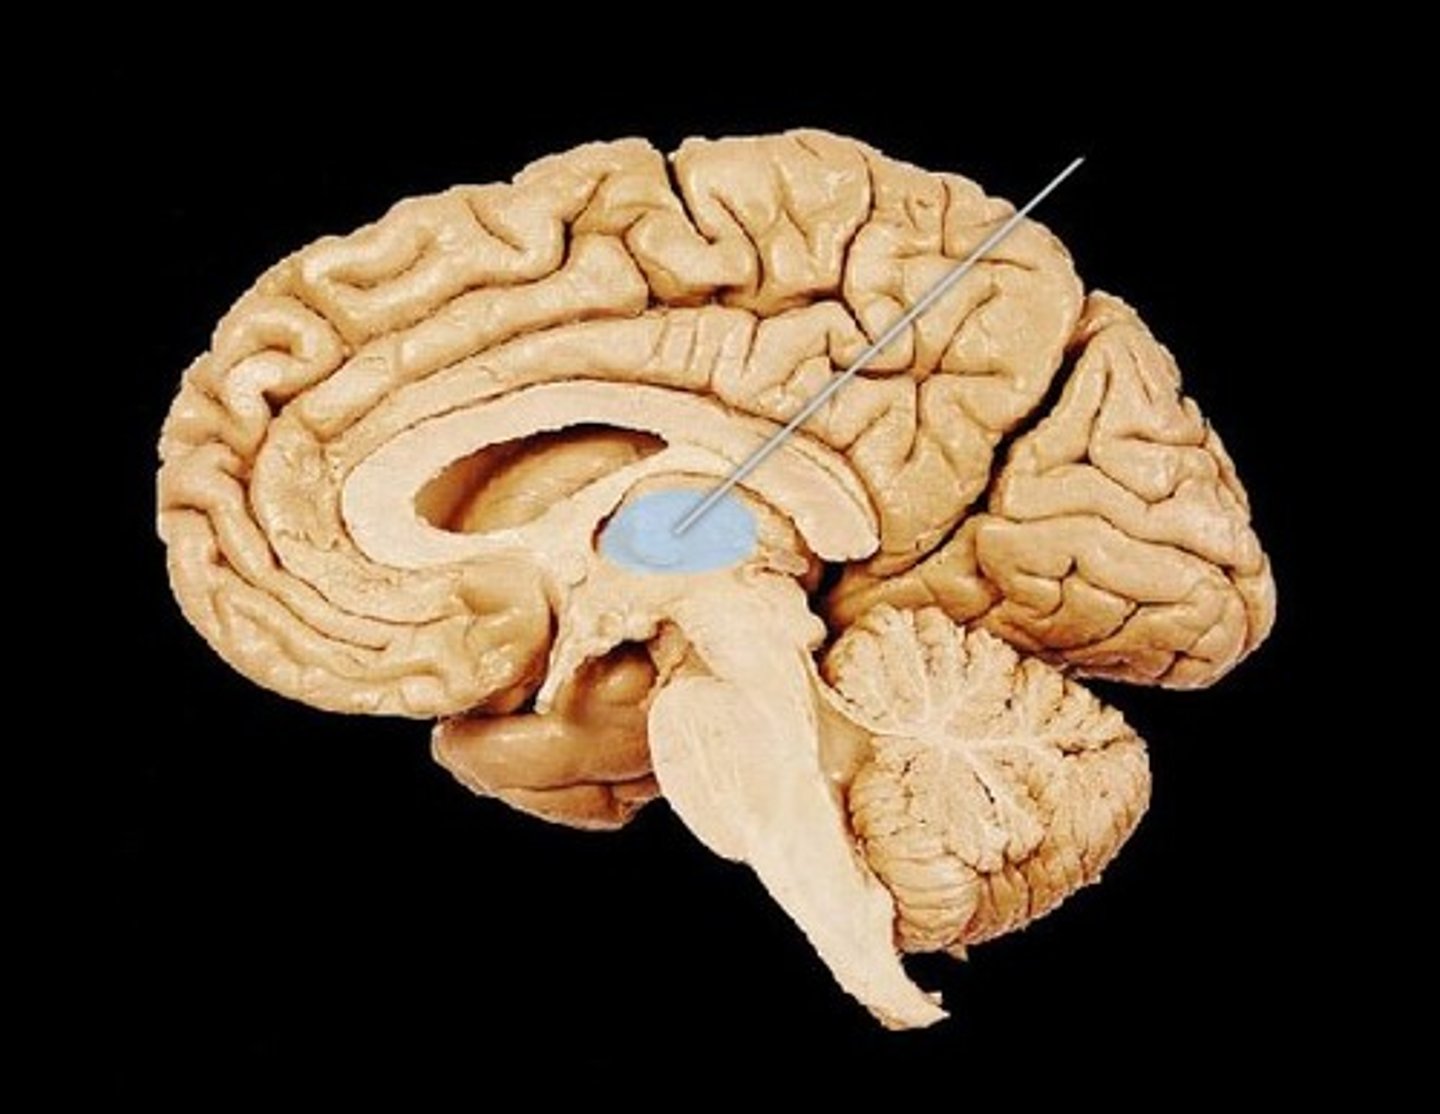

Thalamus

Hypothalamus

hypothalamic sulcus

separates thalamus from hypothalamus

mammillary body

thalamic adhesion

pineal gland - regulates melatonin

interpeduncular fossa - space between cerebral peduncles.

optic chiasm

fornix- a fiber tract that extends from the hippocampus to the mammillary body